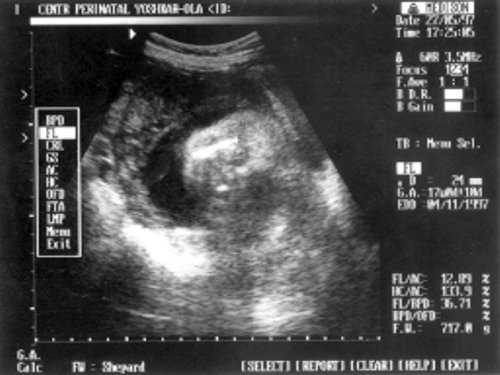

ДБ (длина бедра) = 24 мм - 17 нед. (рис. 2)

- ДБ (длина бедра) = 24 мм - 17 нед. (рис. 2)

Рис. 2. УЗИ плода - бедро.